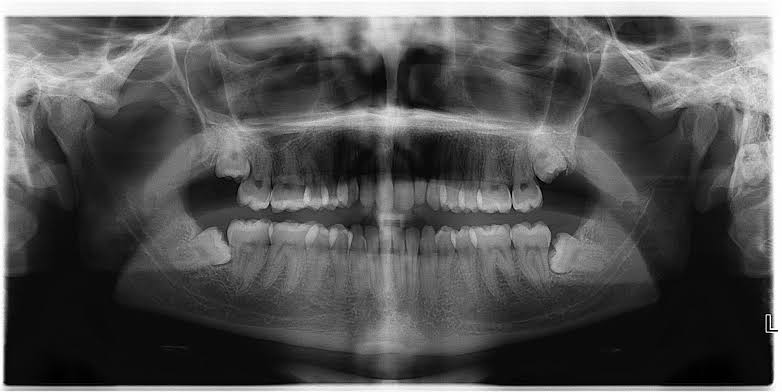

Wisdom Tooth Removal